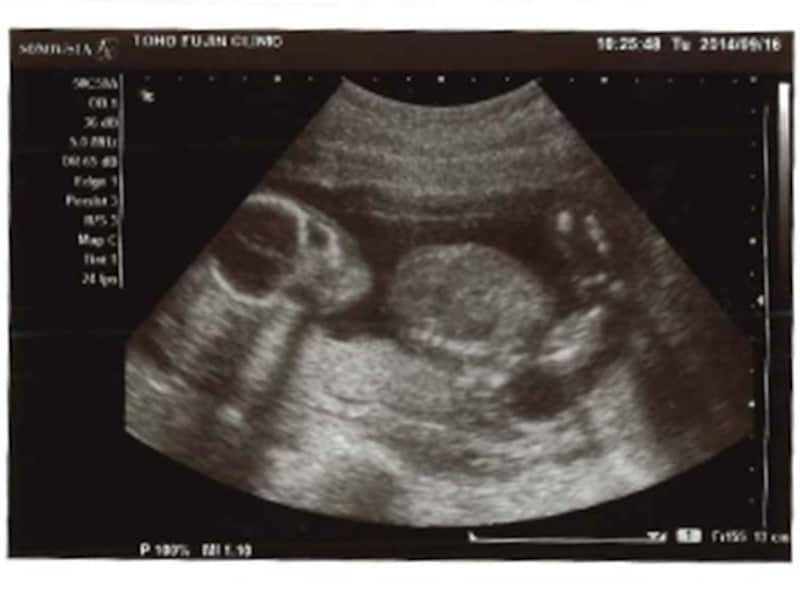

妊娠16週 赤ちゃんの性別が分かる人も!胎児の大きさ・エコー写真

妊娠17週目エコー写真・胎児の大きさ・胎動や性別が分かることも!

妊娠18週目エコー写真・赤ちゃんの大きさ・胎動が分かる人も

妊娠19週目 胎動や性別が分かる人も!胎児のエコー写真・大きさ